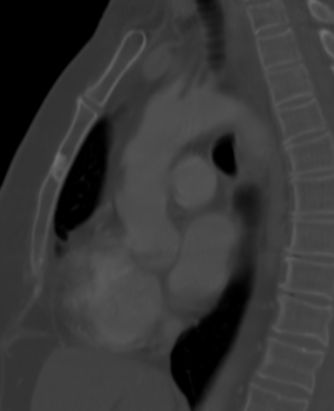

60-jährige Frau mit metastasierten Mammakarzinom. Jetzt

segmentförmige Schmerzen der linken Thoraxwand. das CT zeigt einen diskreten

Weichteiltumor mit Infiltration des Neuroforamens.![]() | |||||||||